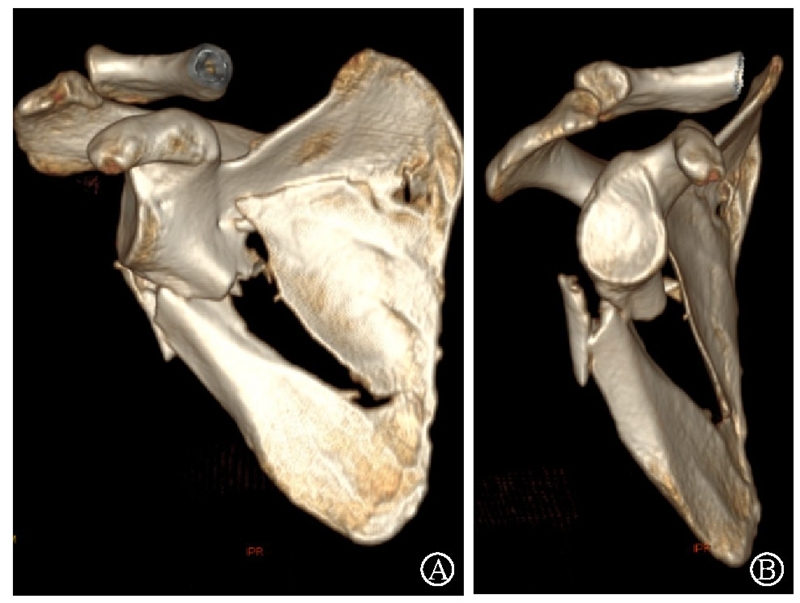

图21 术前CT三维重建示肩胛颈及肩胛骨体部骨折 图A:肩胛骨前面观;图B:肩胛骨侧面观